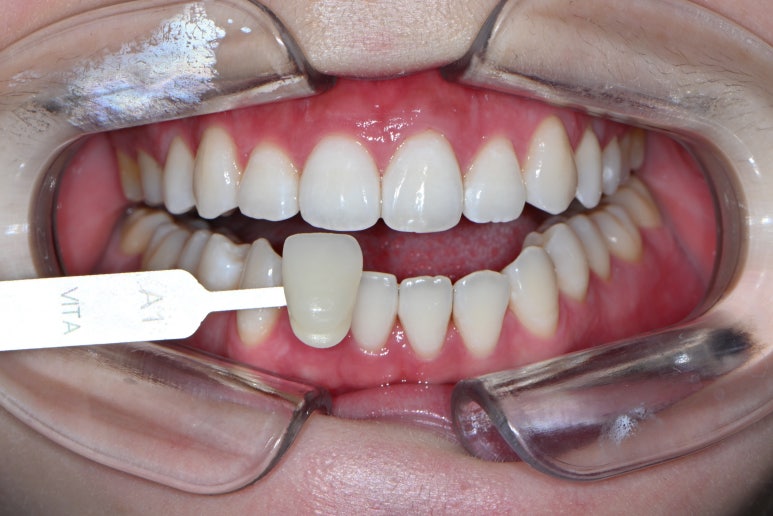

치아미백을 하고난 후 입니다!

VITA Shade guide를 사용했을 때, 치아미백 전에는 A1이랑 비슷했던 색감이 A1을 대면 확실히 더 하얘보이게 바뀐 것을 느끼실 수 있죠...?

전반적으로 노란색을 띄던 감이 많이 사라지고, 이렇게 하얀 톤으로 개선된 것을 보실 수 있을겁니다!!